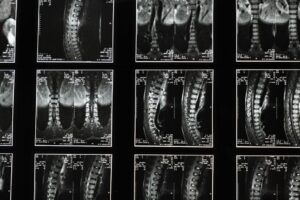

• Diagnostic imaging, if necessary, to pinpoint underlying issues